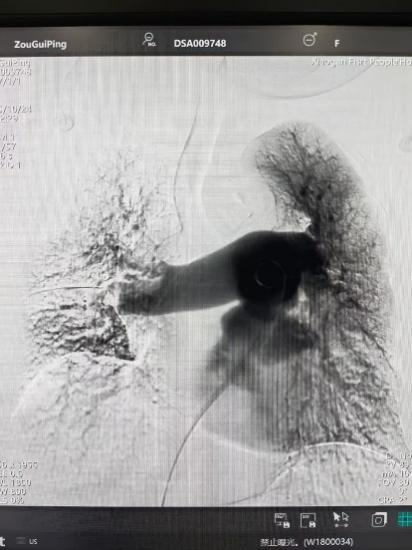

京中网讯(湖北日报网)(通讯员 陈涵)近日,孝感市第一人民医院血管介入团队凭借过硬的介入技术和高科技技术,在医...